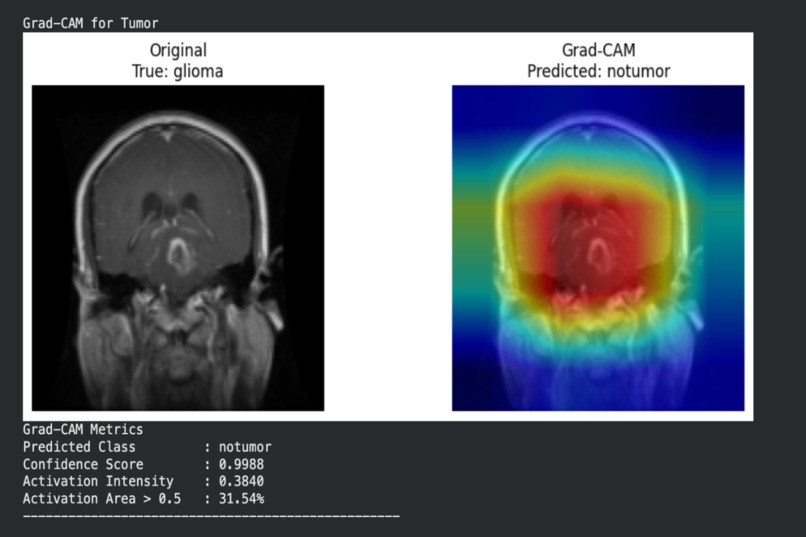

Tumor classification with Grad-CAM analysis

To improve trust and transparency, the system also generates Grad-CAM visualizations that highlight which regions of the brain influenced each prediction.

- Integrated Grad-CAM for visual explanations and added quantitative explainability metrics

- Ensuring model interpretability aligned with known neurological patterns

- Integrated explainability tools that provide clinically meaningful insights